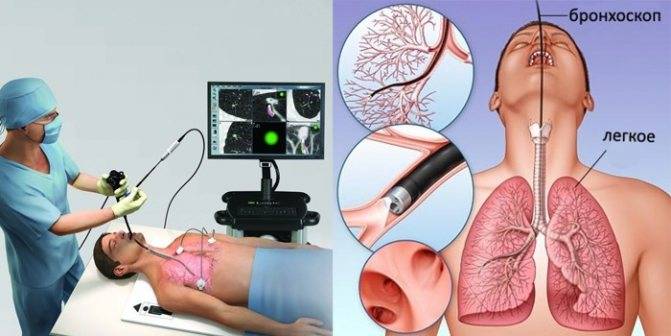

Фотографии и информация о бронхоскопии при туберкулезе